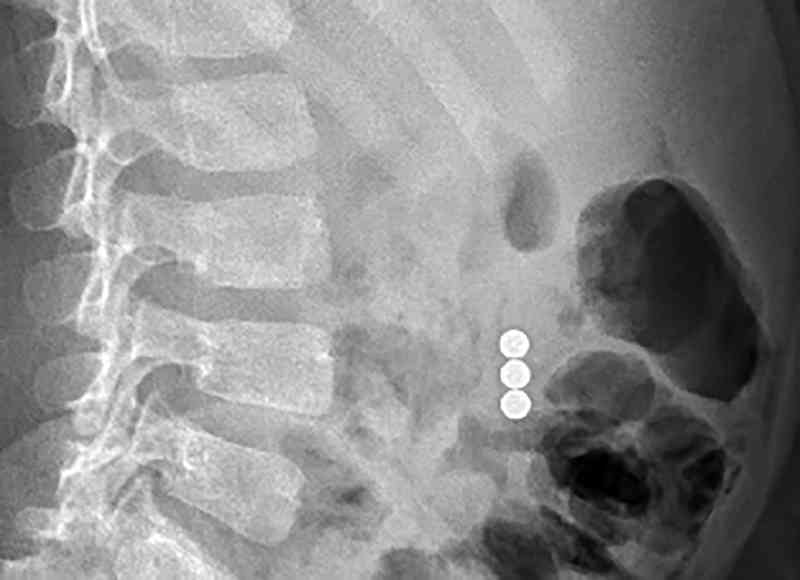

وبعد إجراء فحوصات الأشعة السينية تبين وجود ثلاث قطع مغناطيس في بطن الطفل، وعلى الفور تم استدعاء الدكتور عادل الجنيبي، استشاري جراحة الأطفال لمعاينة الطفل، الذي أجرى فحصًا شاملاً واكتشف أن الطفل قام بابتلاع قطع المغناطيس الثلاثة في أوقات مختلفة ما يفسر تواجدها في مواقع مختلفة في الأمعاء.

قال الدكتور الجنيبي: «تمكنا من استخراج قطع المغناطيس الثلاث بنجاح والتأكد من سلامة واستمرارية الأمعاء باستعمال تقنية الجراحة التنظيرية حيث تم إجراء العملية من خلال ثقوب صغيرة في جدار البطن دون الحاجة إلى إجراء جراحة مفتوحة مع شقوق طويلة. وكانت قطع المغناطيس الثلاثة متوزعة بين المعدة والأمعاء الغليظة وتجذب بعضها البعض مما سبب انسداداً في الأمعاء كما تمت ملاحظة بداية تكوّن انثقاب في الأمعاء الدقيقة».